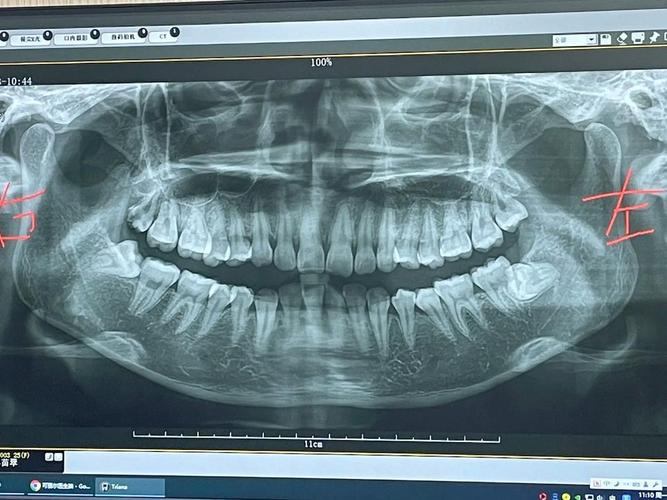

- 收益远大于风险: 片子能帮助医生发现肉眼看不见的早期蛀牙、牙槽骨吸收、埋伏牙、囊肿等问题,为制定精准、有效的治疗计划提供关键依据,其带来的健康收益远远大于微乎其微的辐射风险。